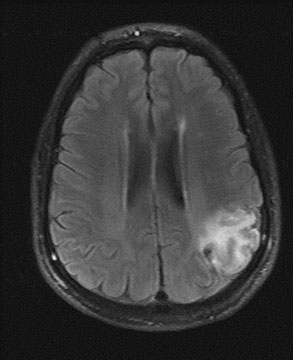

In the evaluation of extracranial large vessel disease, mainly carotid disease, ultrasound is the initial indicated study. It is commonly available, relatively inexpensive, and accurate. In addition, compared to other vascular imaging methods, it has the ability to directly image and characterize the plaque. Certain plaque characteristics may predict an increased risk of embolization. For example, the presence of an ulcer at the plaque surface may promote the formation of thrombus that can secondarily embolize, while a hypoechoic plaque, representing either intraplaque hemorrhage or a lipid-rich plaque, is associated with the potential for plaque destabilization.79,80 Carotid artery ultrasound has a sensitivity of 90% to 95% and specificity of 85% compared to catheter angiography.81 However, ultrasound may be unable to detect high-grade stenosis and mistakenly diagnose a carotid occlusion in 5% of cases. It is important to make this distinction as a patent vessel may be amenable to a revascularization procedure. Although power Doppler and echo-contrast agents may improve the odds of a correct diagnosis, for now it is standard practice to corroborate carotid occlusions with another imaging modality such as MRA, computed tomographic angiography (CTA), or conventional catheter angiography. MRA is an evolving technology comparable in accuracy to ultrasound, with the advantage of being able to image the distal carotid. In the past, there was a risk of overestimation of carotid stenosis by MRA, and beyond 70% stenosis, the absence of signal (flow gap) impeded adequate quantification of narrowing.82 Evolution in MRA technology and the use of contrast agents has improved the yield of this diagnostic method. Catheter angiography is the gold standard for carotid disease, but has inherent risks, with approximately 1% risk of stroke, although probably less in experienced centers. Figure 2 demonstrates the use of imaging technology in carotid disease.

Fig. 2. This 48-year-old diabetic man suddenly developed confusion and clumsiness of the right hand. On examination, he had inability to identify objects by touch and difficulty identifying the right from the left. A. Fluid attenuated inversion recovery (FLAIR) MRI shows a left parietal cortical infarct. Two potential embolic sources were noted: a left ventricular apical clot was seen on echocardiography from a presumed recent silent myocardial infarction, and ultrasound and subsequent angiography confirmed a significant left internal carotid stenosis. B: A 70% left internal carotid artery origin stenosis is shown on angiography. Monitoring both middle cerebral arteries with transcranial Doppler showed microembolic signals only over the left, suggesting that the carotid atherostenotic plaque was active or destabilized. C: An interruption (arrow) of the normal Doppler flow pattern of the middle cerebral artery is shown, representing a microembolic signal. The artery was stented rather than revascularized by endarterectomy because of the recent myocardial infarction. D: A patent revascularized carotid is revealed by ultrasound; note the struts of the stent.

Carotid angioplasty and stenting is a novel endovascular approach to revascularizing the carotid artery. As a technique, it is in its infancy, and catheter technology and distal protection devices to prevent periprocedural strokes are constantly evolving. To date, no randomized study has shown superiority of this technique over surgical endarterectomy in the average patient,83,84 although direct comparisons between endarterectomy, and angioplasty and stenting are currently underway.85 However, high-risk patients appear to do better with endovascular approaches.86 In the author's opinion, for now angioplasty and stenting should be reserved for symptomatic patients who cannot undergo surgery or generalized anesthesia because of cardiac or pulmonary conditions. Certain situations, such as radiation-induced arteriopathy, contralateral occlusion or high-grade stenosis, or contralateral vocal cord paralysis, are relative contraindications to endarterectomy; in their presence angioplasty and stenting is an appropriate therapeutic choice. An example of carotid stenting is shown in Figure 2.